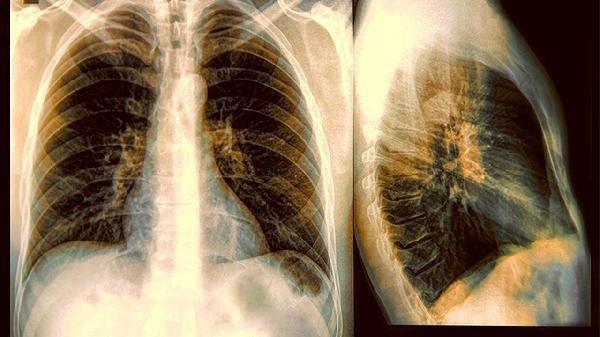

Người đàn ông bị ung thư phổi giai đoạn cuối dù sống lành mạnh, 3 thói quen trong phòng ngủ là "thủ phạm" -

09/02/2026 14:57Người đàn ông bị ung thư phổi giai đoạn cuối dù sống lành mạnh, 3 thói quen trong phòng ngủ là "thủ phạm"

Khi khai thác kỹ thói quen sinh hoạt, đặc biệt là các hoạt động vào buổi tối, nhiều yếu tố tưởng chừng vô hại dần được phát hiện. Những hành vi quen thuộc này có thể âm thầm gây tổn thương đường hô hấp trong thời gian dài mà không ai ngờ tới.

Theo Tổ chức Y tế Thế giới (WHO), 10–20% người mắc ung thư phổi không hề hút thuốc. Nguyên nhân có thể liên quan đến ô nhiễm không khí trong nhà, khí radon, khói bếp, môi trường nghề nghiệp hoặc các thói quen sinh hoạt kéo dài nhiều năm. Trường hợp này cho thấy, những yếu tố diễn ra vào ban đêm cũng có thể đóng vai trò quan trọng.

Sức khỏe phổi không chỉ phụ thuộc vào việc hút thuốc hay không, mà còn chịu ảnh hưởng lớn từ môi trường sống và thói quen hằng ngày. Chỉ cần thay đổi một vài thói quen vào buổi tối, bạn đã có thể tạo ra khác biệt lớn cho sức khỏe lâu dài.